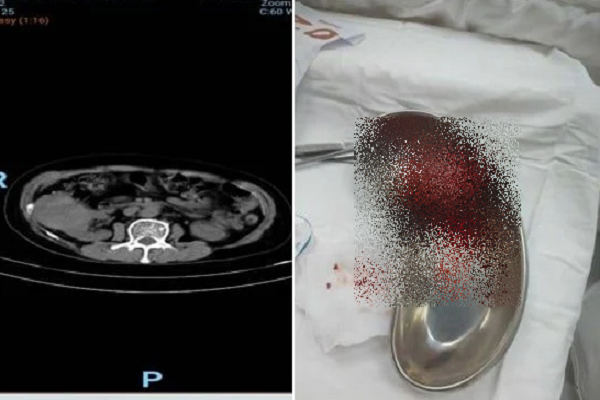

Kết quả chụp CT trước phẫu thuật (hình bên trái) và khối u thận sau khi lấy ra khỏi cơ thể bệnh nhân - Ảnh: BVCC

Các bác sĩ Bệnh viện Nhân dân 115 thực hiện siêu âm bụng thì phát hiện một khối u kích thước 75 x 60mm ở cực trên thận phải nữ bệnh nhân. Sau khi chụp CT có tiêm cản quang, khối u được chẩn đoán nghi ngờ là ung thư biểu mô tế bào thận (RCC) chưa có dấu hiệu xâm lấn ra ngoài thận trên hình ảnh học.

“Rất may là bệnh nhân này bất ngờ được phát hiện kịp thời, các bác sĩ đã tiến hành can thiệp tắc mạch chọn lọc để giảm lượng máu nuôi khối u, sau đó thực hiện phẫu thuật nội soi cắt khối u bảo tồn phần nhu mô thận còn lại. Nhờ đó, bệnh nhân giữ được chức năng thận tối ưu và phục hồi nhanh chóng sau phẫu thuật”, bác sĩ Minh cho biết thêm.